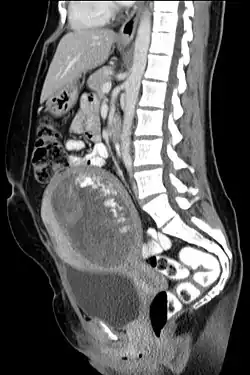

Hydatidiform mole on CT, sagittal view

The diagnosis is strongly suggested by ultrasound (sonogram), but definitive diagnosis requires histopathological examination. On ultrasound, the mole resembles a bunch of grapes ("cluster of grapes" or "honeycombed uterus" or "snow-storm").[14] There is increased trophoblast proliferation and enlarging of the chorionic villi, and angiogenesis in the trophoblasts is impaired.[15]